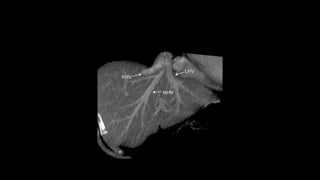

HEPATIC VEINS

• Venous blood of the liver is mainly

collected by the hepatic veins, which

drain into the IVC.

• Has three main venous branches: the

left, the right and the middle one.

• Hepatic veins are not encompassed

by a surrounding connective tissue

sheath, as their tunica adventitia is in

direct contact with the liver

parenchyma

HEPATIC VEINS • Venousblood of the liver is mainly collected by the hepatic veins, which drain into the IVC. • Has three main venous branches: the left, the right and the middle one. • Hepatic veins are not encompassed by a surrounding connective tissue sheath, as their tunica adventitia is in direct contact with the liver parenchyma